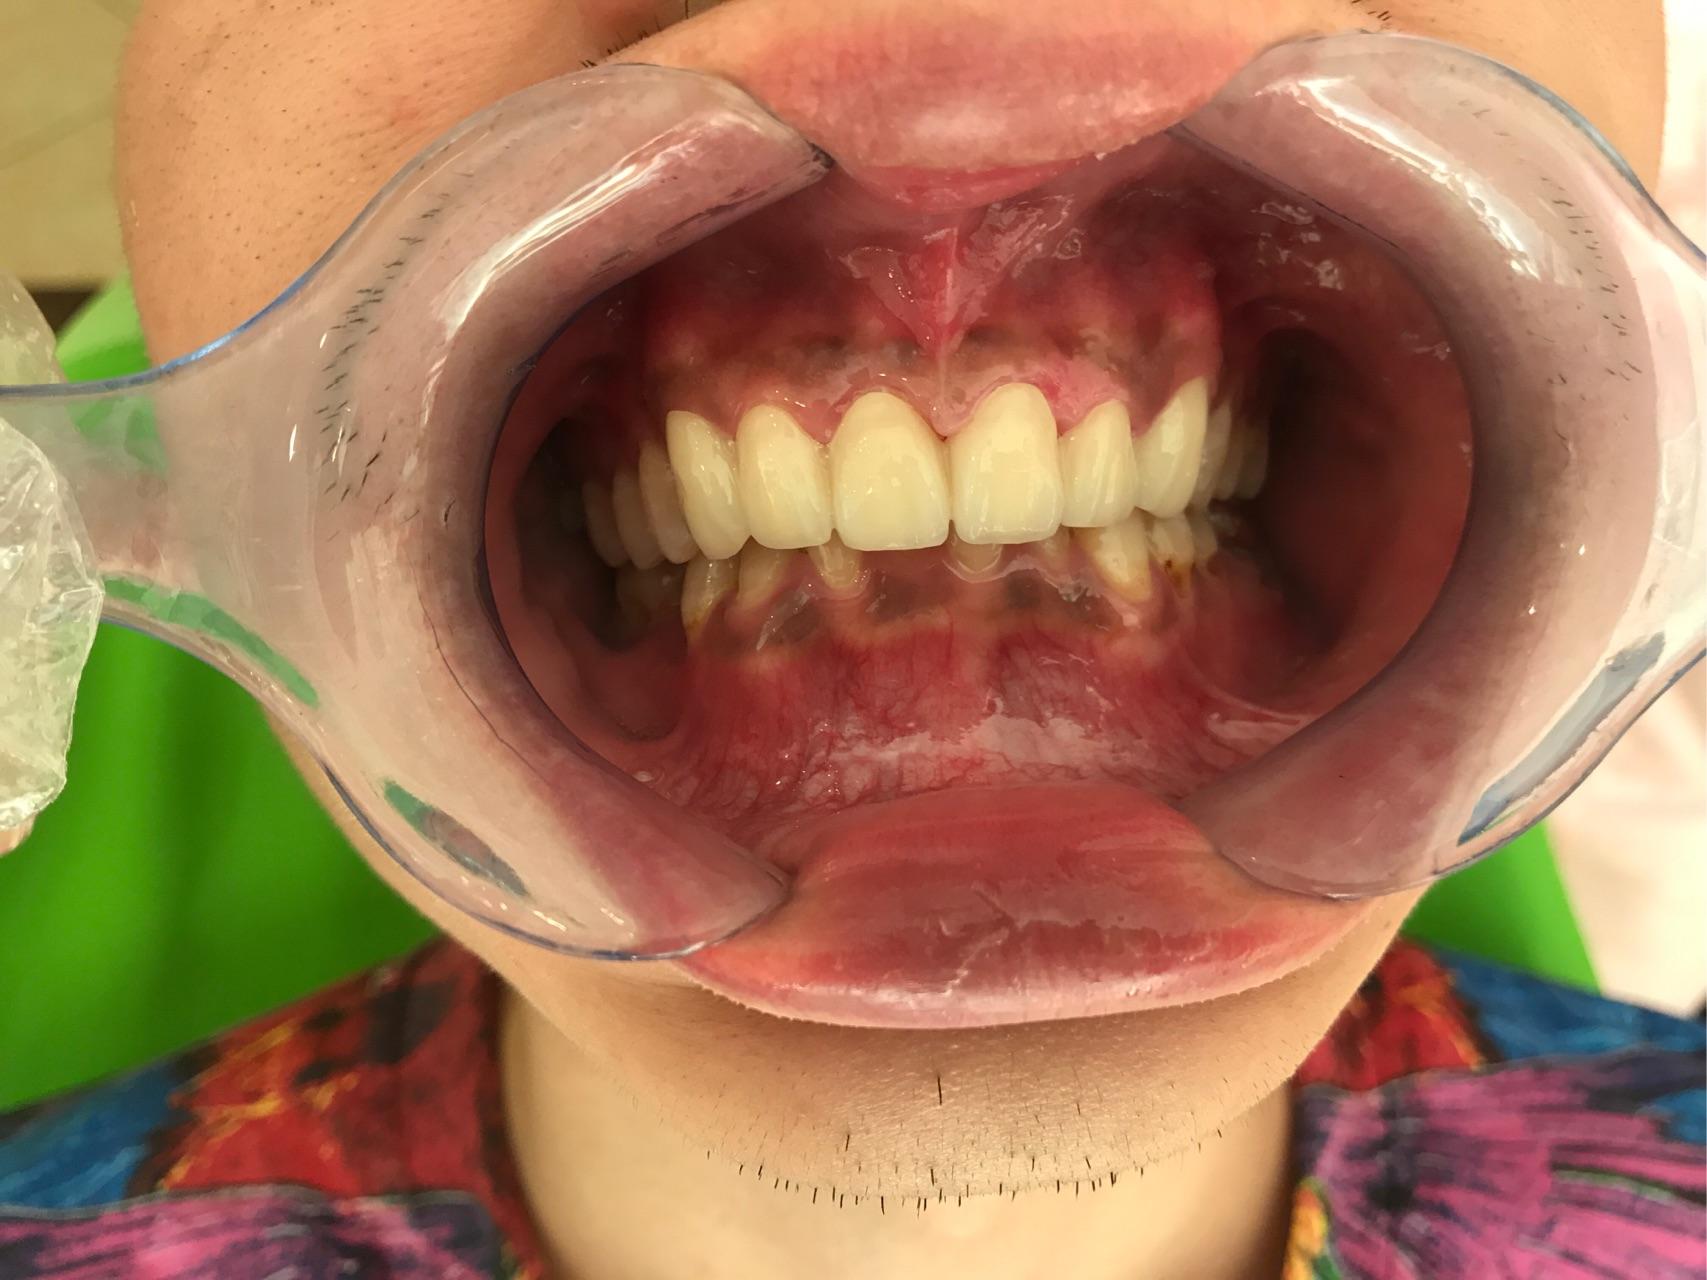

牙医碰见最烂的牙有多烂?

牙医碰见最烂的牙有多烂?

牙医碰见最烂的牙有多烂?

盘点葫芦岛口腔牙医遇见最烂的牙到底有多烂(

牙医碰见最烂的牙齿到底有多烂?

牙医碰见最烂的牙有多烂?

牙医碰见最烂的牙有多烂?

牙医碰见最烂的牙有多烂? - 知乎

牙医碰见最烂的牙有多烂? - SHINeelion 的回答

牙医碰见最烂的牙有多烂? - 曹先生的回答 - 知

牙医碰见最烂的牙有多烂?

牙医碰见最烂的牙有多烂? - 知乎

牙医碰见最烂的牙有多烂? - 知乎